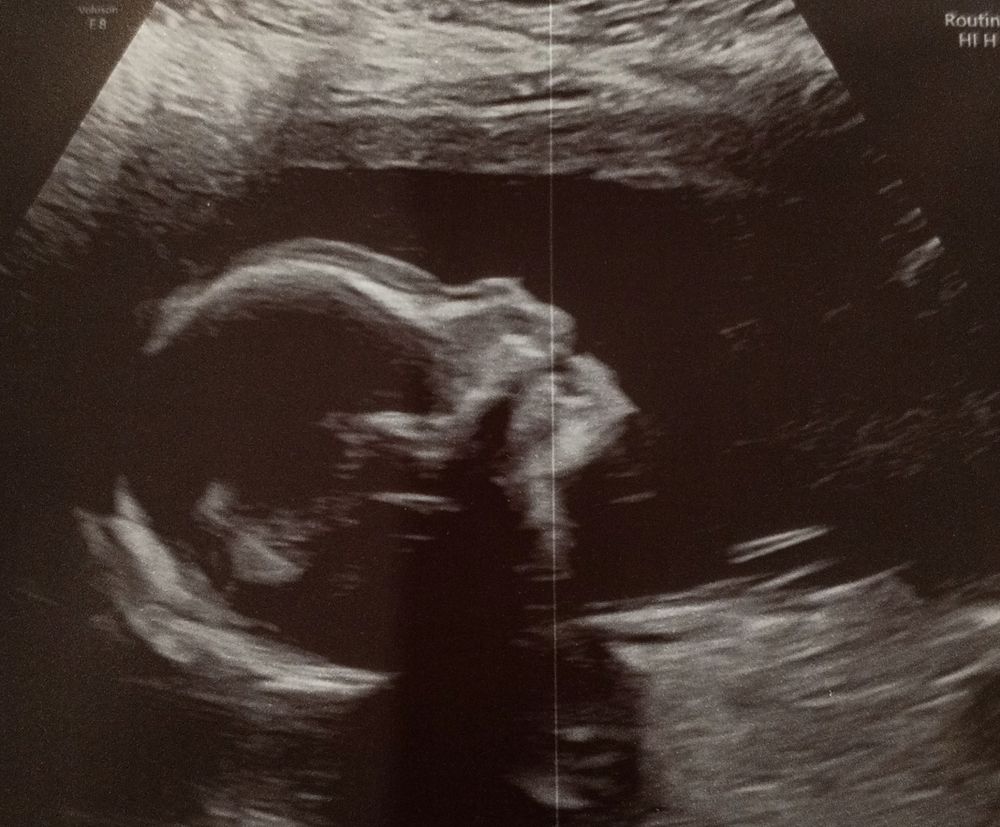

Омфалоцеле 20 21 неделя

Посетила повторный консилиум в пц Середавина, в этот раз с бумагой от мск что нас берут на роды и операцию. Естественно все там выдохнули с облегчением, пожелали всего хорошего и отправили во свояси. В рамках консилиума было узи, которое показало улучшение всей ситуации в целом, но я всегда проверяю, хотя бы 2 мнения собираю, и сегодня была у своего платного узиста. К моему счастью и удивлению действительно все стало лучше. Отодвинулись от нижней границы нормы по водам, бедра догнали по размерам относительно тела, и в целом рост и вес стал заметно увеличиваться. Сейчас мартышка весит почти 400 грамм. Что для меня было самым удивительным, что перестала расти грыжа, пока даже немного уменьшилась, возможно из за того, что печень, которая все это время была в составе грыжи опустилась в животик. Сильно не радуюсь, тк органы еще могут гулять туда сюда, но всё-таки информация приятная и если такой прогресс сохранится, то малышке будет легче пережить операцию и восстановиться. На будущей неделе пройду повторно эхокг, зайду на прием в жк чтоб отдать все результаты и надеюсь с врачами в этом году будет окончено, можно будет наслаждаться беременностью и подготовкой к новому году. Даже настроение улучшилось. В общем новостей не много, но они хорошие, а это главное.